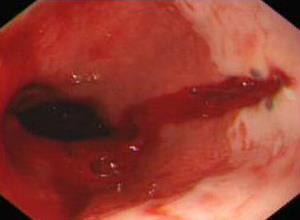

简介食管贲门粘膜撕裂综合征又称Mallory-Weiss综合征,是指因频繁的剧烈呕吐,或因腹内压骤然增加的其它情况(如剧烈咳嗽、举重、用力排便等),导致食管下部和/或食管胃贲门连接处粘膜撕裂而引起以上消化道出血为主的症候群。